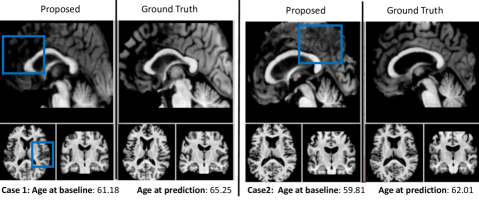

For completeness, Fig. 1 shows an example of an entire simulation obtained using the full configuration of 4D-DANI-Net. Expected neurodegeneration is apparent in the sequence, including ventricular expansion, hippocampus contraction, and cortical thinning.

Our results show that the model can generalize well to new data, with only slightly reduced performance on average. Generally speaking, AI model generalization is known to be a challenge, particularly when the training set is not fully representative of the target distribution. Indeed, reduced performance is expected here due to cohort differences, e.g., the distributions of age and follow-up duration, which differed between the ADNI and OASIS-3 datasets. We found that performance declined the most for large regions of the brain such as the cortical surface, which is well known to vary considerably between individuals, suggesting that personalization is the most challenging aspect of model generalization here. To demonstrate this, we show in Fig. 10 two cases where the model did not generalize well. A moderate drop in image quality is evident in large regions of the obtained images. In particular, in both cases of Fig. 10, the images are blurred due to low numbers of individuals in the training set aged in the range between 60-62. Despite the performance reduction in such outlier cases, our model performed quite well in most cases.